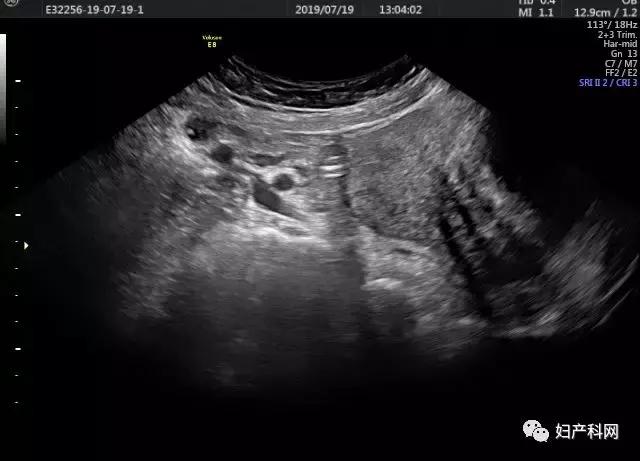

囊肿术后